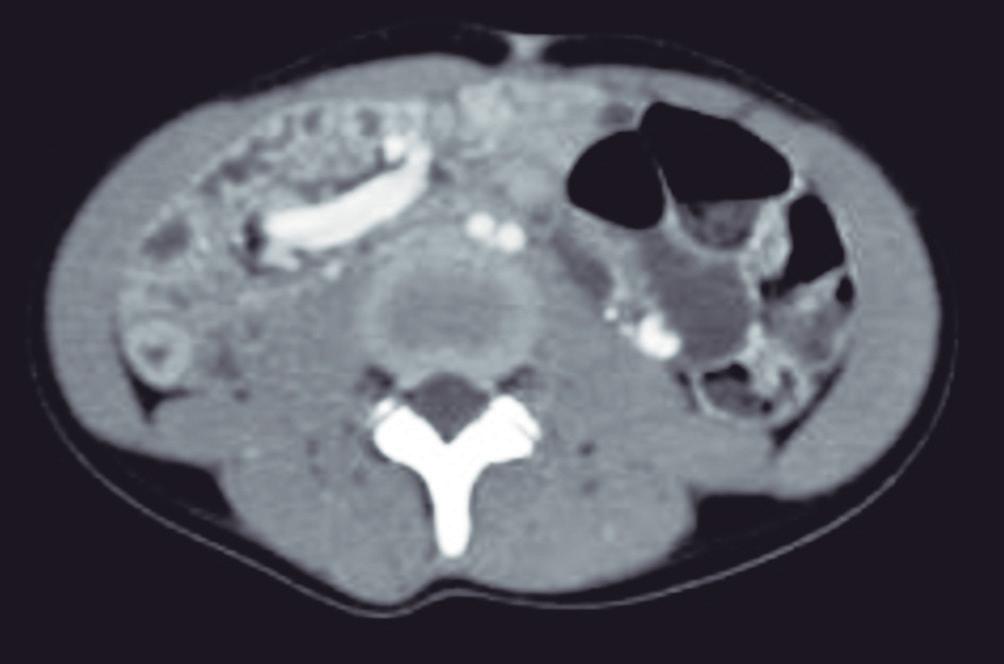

Adenoma hepatocelular asociado a inactivación del factor hepatocitario nuclear α1 (AHC-HNF1α)

Este subtipo, el segundo en frecuencia, suele asociarse al uso de ACO y también en pacientes con adenomatosis y poliposis adenomatosa familiar. El HNF1α codifica un factor de transcripción clave para la diferenciación, y para el metabolismo y transporte de lípidos en los hepatocitos. Estas lesiones se caracterizan por su curso indolente con riesgo escaso o nulo de sangrado o de malignidad, y por la abundancia de lípidos en sus células.11 Esta última característica es la que permite en muchos casos hacer un diagnóstico confiable de este subtipo de adenoma. En la TCMC

suelen ser hipodensos debido al contenido lipídico. No obstante, la RM merced al empleo de la secuencia GRE T1 dual, permite reconocer en forma específica la presencia de lípidos intravóxel, manifestando una caída de la intensidad de señal en la imagen fuera de fase con respecto a la imagen en fase. Por otra parte, su refuerzo poscontraste es menos intenso que el de los otros subtipos de adenoma. La baja densidad en la TCMC y baja señal en imágenes T1 con supresión grasa puede llevar a la errónea interpretación de lavado en imágenes tardías y por ende, simular un CHC. Este subtipo de adenoma tampoco expresa transportadores OATP B1 y B3. (Figura 7)

A: Imagen ponderada en T2 con supresion grasa que muestra un nodulo hipointenso con respecto al parenquima con bordes netos. B: Imagen ponderada en T1 dual en fase que demuestra a la lesion con una señal levemente hiperintensa. C: Imagen ponderada en T1 dual fuera de fase muestra caida de la intensidad de señal en forma difusa de la lesion confirmando la presencia de grasa microscopica. D: Imagen ponderada en T1 poscontraste en fase arterial, la lesion presenta refuerzo mayor al parenquima pero de menor intensidad que el de otras lesiones hepatocelulares. E: Imagen ponderada en T1 poscontraste en fase venosa portal que demuestra hipointensidad difusa de la lesion. Si bien podria interpretarse este hallazgo como lavado, dicho comportamiento obedece a la supresion grasa inherente a esta secuencia y no a un lavado verdadero. F: Imagen ponderada en T1 obtenida en fase hepatobiliar que muestra a la lesion hipointensa sin captacion del contraste.

Adenoma hepatocelular asociado a mutación β-catenina

Este subtipo es más frecuente en varones y además el que conlleva mayor riesgo de malignidad.11 Se han descripto dos variantes: exón 3 y exón 7/8, la primera implica mayor riesgo. Sus características por imágenes no son específicas. Se ha descripto la presencia de zonas hiperintensas de bordes difusos en T2 y una cicatriz de bordes mal definidos. Puede verse grasa en su seno pero en escasa cantidad y de distribución focal y parcheada, en contraste con el AHC-HNF1α, que presenta abundante y extensa cantidad de lípidos. Demuestra hiperrefuerzo en fase arterial, puede tener lavado y cápsula, solapando asi sus características con las de un CHC. Este

subtipo puede expresar transportadores OATP y por lo tanto, ser isointenso o hiperintenso en la fase hepatobiliar con CHE.